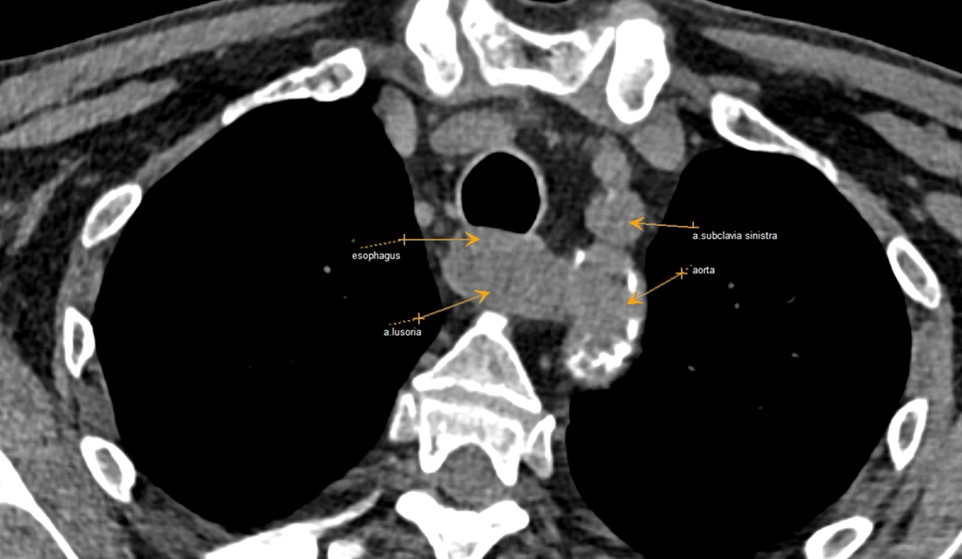

Рисунок 1 - Пациент А. 1955 г.р., аксиальная проекция КТ органов грудной клетки

Примечание: cтрелками указаны a. lusoria, отходящая от аорты дистальнее левой подключичной артерии, позади пищевода